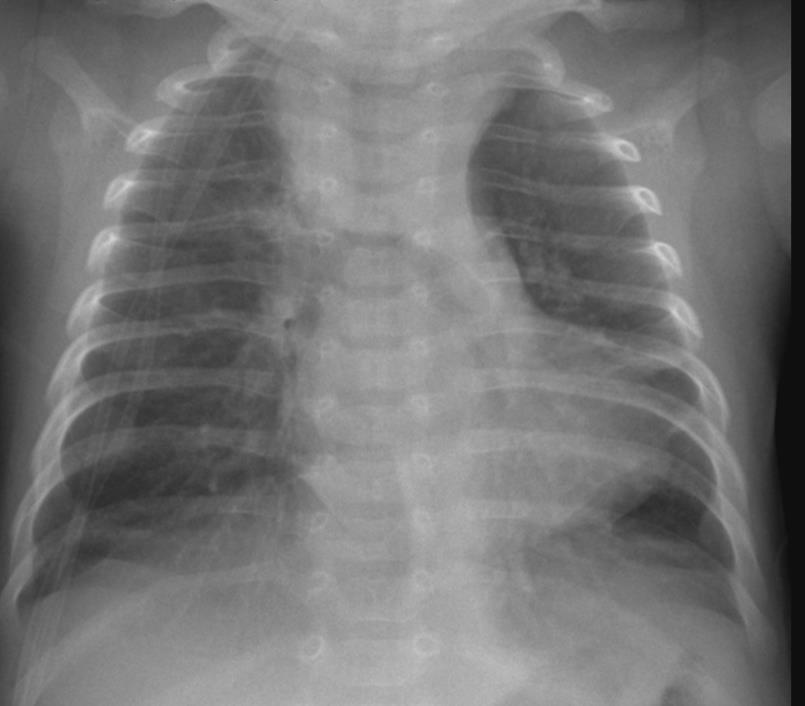

Imaging of Covid 19 infection in children CXR 8 38% 3% 51% 8%

Consolidation 35%

Collapse 3%

PeriBronchial thickening

51%

Hyperexpansion 7%

Effusion 4%

Imaging of Covid 19 infection in children CXR 9 C O V I D

Birmingham

Covid 19 CXR Imaging of Covid 19 infection in children